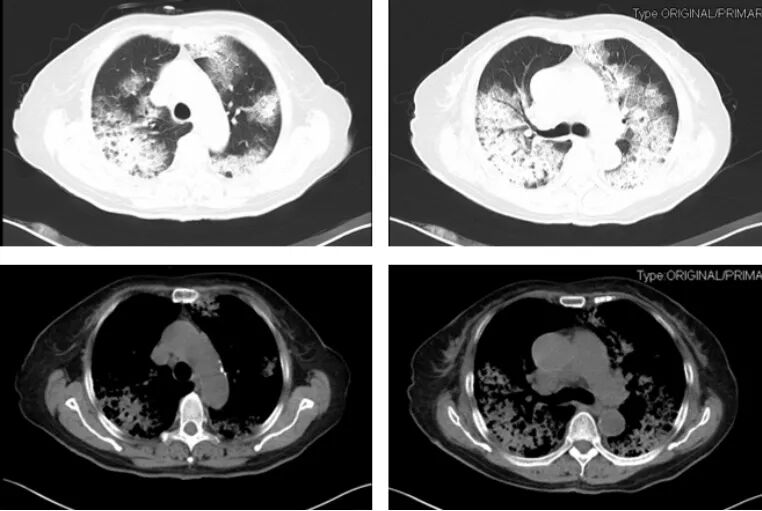

第三步,结合患者病史特征。虽然影像学特征能够提供鉴别方向,但单独影像学很难具体诊断某种疾病,因此需结合患者病史特征,包括详细的问诊及查体等。首先,我们需考虑疾病起病缓急,以双肺GGO为主要表现急性起病的疾病包括肺水肿、肺出血、PCP、支原体肺炎、病毒性肺炎、急性间质性肺炎、急性嗜酸性粒细胞肺病、早期过敏性肺炎、药物反应、淋巴瘤等;而慢性起病的疾病包括过敏性肺炎、DIP、RB-ILD、细胞性非特异性间质性肺炎、肺泡蛋白沉积症、细支气管肺泡癌(原位腺癌)、机化性肺炎、结节病。以下图病例为例,患者因重度Ⅰ型呼吸衰竭就诊,双肺表现为铺路石征及地图样改变,如果急性起病,我们可能首先会考虑PCP等可能,而患者4年缓慢进展的病史提示肺泡蛋白沉积症等慢性进展性疾病的可能性更大,而最终的肺泡灌洗液病理证实肺泡蛋白沉积症。